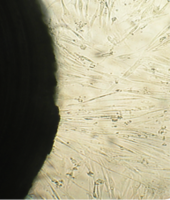

Вид монослоя и структура клеток не отличались от обычных в течение всех четырех суток наблюдения (рис. 32).

Количество поврежденных клеток было в пределах 2-5%.

Плотность монослоя на 2-е сутки в опыте составляла 1519 клеток/ммІ, в контроле - 1191 клеток/ммІ.

На четвертые сутки эксперимента клетки в контрольной чашке достигают плотности насыщения, которая равна для данной культуры 2020 клеток/ммІ.

Культура переходит в стационарную фазу роста, так как вступает в действие контактное торможение (нетрансформированные фибробласты в культуре растут в виде монослоя).

В связи с этим в ростовой среде несколько увеличивается количество слущенных клеток.

Плотность клеток в опытной чашке на 3 и 4 сутки превышает контрольный показатель.

Клетки лежат очень плотно друг к другу, тела их становятся короче, отростки укорачиваются и уменьшаются в количестве, но цитоплазма остается гомогенной, цитолемма и нуклеолемма четко контурируют.

В ядрах большинства фибробластов присутствует одно ядрышко.

Количество поврежденных клеток остается небольшим.

Это свидетельствует об умеренной стимуляции пролиферации фибробластов в культуре под влиянием недеминерализованной спонгиозы (таб. 9.).